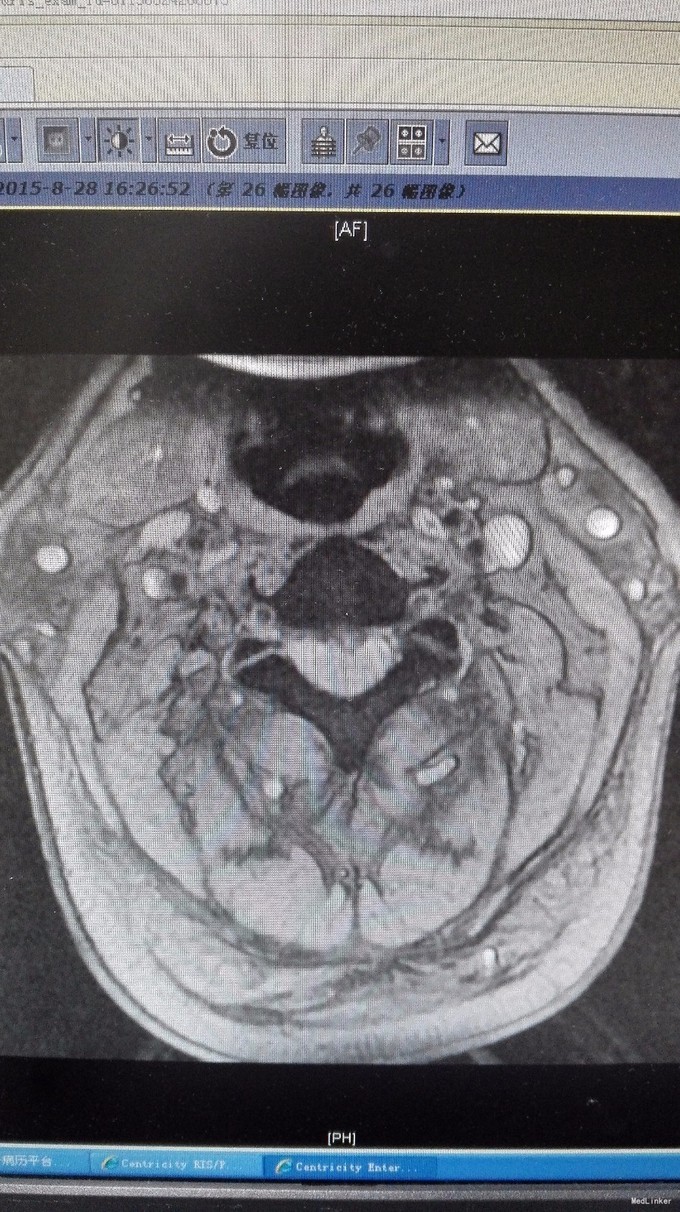

主诉:双手第2、3指尖麻木1年,加重伴双下肢沉重感4月。 病史:1年前出现双手食指、中指指尖麻木,未予以治疗,4月前出现双下肢沉重感,予以腰椎按摩后双下肢症状有所缓解,但双下肢仍有沉重感,右下肢较重,在外院诊治为颈椎病,建议手术治疗,患者拒绝,为求进一步诊治,特来我院就诊,门诊拟混合型颈椎病收入我科住院治疗。

查体:双手麻木感,肱三头肌肌腱反射活跃,左侧髂腰肌4级,臂丛牵拉实验阴性,椎间孔挤压实验阴性。 辅查:CT:C2-7椎间盘突出,继发性椎管狭窄,OPLL,OFL。

诊断:混合型颈椎病(脊髓型+神经根型) 治疗:颈后路3-7单开门椎管扩大成型术(锚定法)